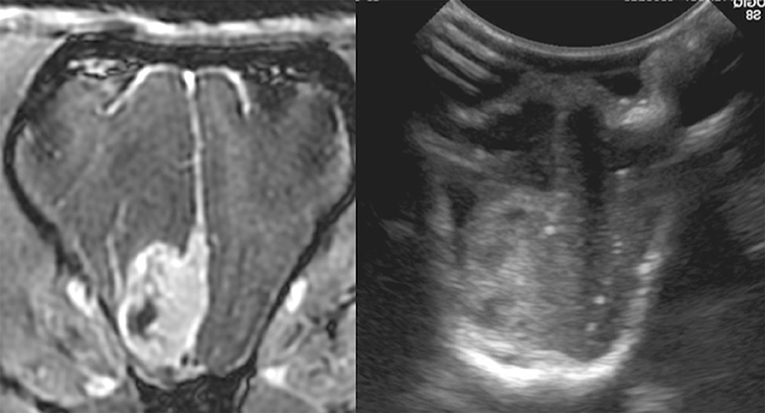

FIGURE 7

Figure 7. Case 36. (A) Sagittal and transverse magnetic resonance images of a cat that suffered a skull fracture 6 months before presentation and presented for a sudden onset of generalized seizures. The injury site consisted of fluid-filled areas and devitalized cortical tissue. (B) At surgery, the ultrasound identified the fluid-filled areas and adjacent unaffected cerebral tissue.